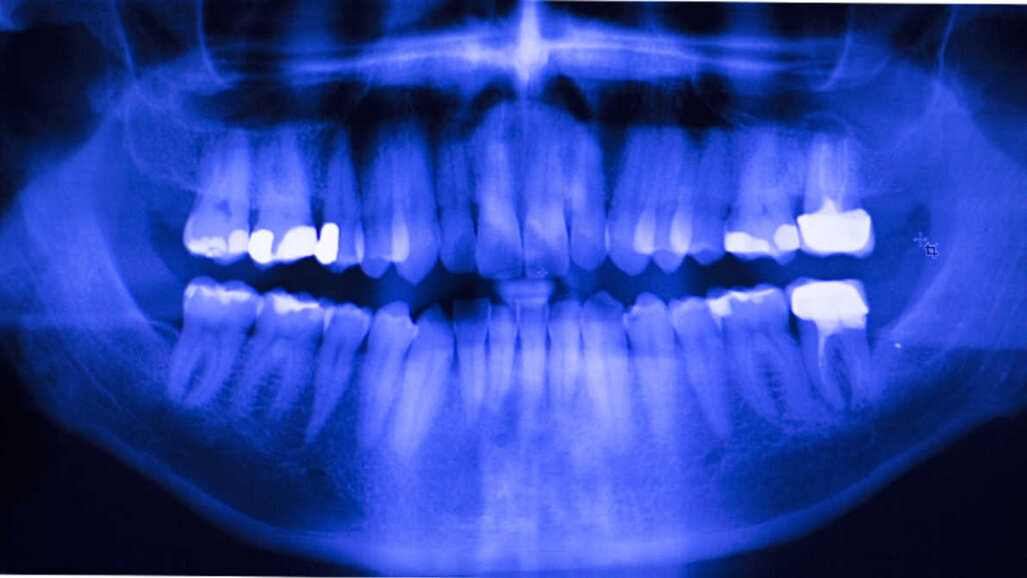

Uma tabela de comparação de materiais restauradores foi criada a fim de abordar as diferentes opções de restauração direta e indireta. Vários parâmetros foram considerados, incluindo o local da restauração, a condição da estrutura dentária remanescente, a profundidade e tamanho da lesão, a possibilidade de isolar, fatores de risco de cárie, considerações econômicas e as propriedades físicas e clínicas dos diferentes restauradores opções. A tabela de comparação foi posteriormente transformada em uma árvore de decisão e, após quatro etapas adicionais, a árvore de decisão foi finalizada e aprovada.

A árvore de decisão foi adaptada em uma ferramenta educacional on-line de fácil utilização que visa facilitar a identificação dos materiais restauradores mais adequados para cada situação. O conselho baseado no consenso dos especialistas orienta os médicos passo a passo na identificação dos materiais restauradores e procedimentos adequados, dependendo da situação clínica, levando em consideração os principais fatores de tratamento, como tempo e eficiência de custo, estética, conforto e expectativas do paciente, e preservação da estrutura dentária.